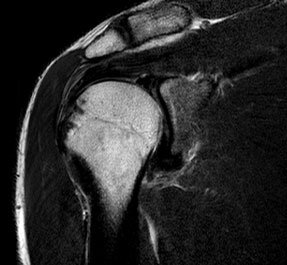

MRIは強力な磁石と電波を使って人体の断面像を得る検査です。CTと比較してX線被爆がない、様々なコントラストの画像が得られるという利点があります。異なる組織や病変を区別しやすい画像を作り、病変の特徴を知ることができます。国内で先駆けてマルチトランスミット法という画質改善法を採用し、これまでのMRIでは診断の難しかった関節軟骨損傷や靭帯損傷などの診断が可能となりました。